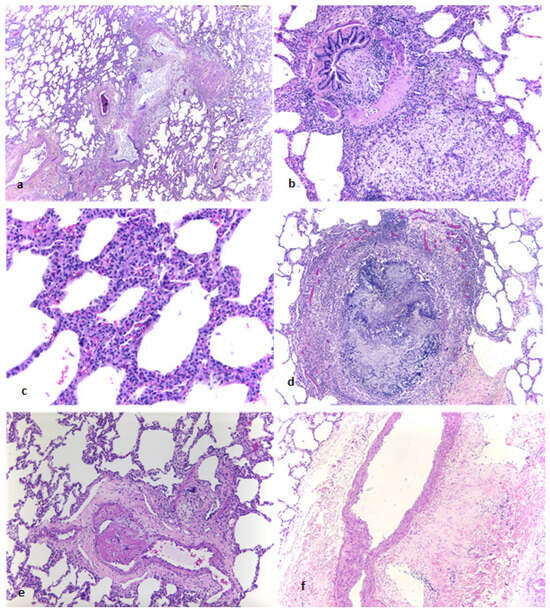

In the absence of contraindications and since the patient had a high lung allocation score (LAS), a bilateral sequential lung transplantation was performed. Prior to lung transplantation, the patient received tocilizumab, an IL-6 receptor monoclonal antibody, with the rationale of significantly reducing dominant HLA antibodies in order to prevent antibody-mediated rejection, consistent with evidence supporting IL-6 blockade in this setting [12]. The specimens of the explanted lungs revealed bronchiolitis obliterans characterized by fibrous obliteration of small bronchioles, associated peribronchiolar lymphocytic inflammation and occasionally a residual aspergilloma (Figure 5). These features confirmed the diagnoses of bronchiolitis obliterans.

Figure 5.

Explanted lung showing bronchiolitis obliterans and associated findings. (a) H&E, low-power: bronchiolar lumina obliterated by fibrous tissue with adjacent foamy macrophages and hyalinization. (b) H&E, intermediate-power: aggregates of foamy macrophages in peribronchiolar tissue. (c) H&E, high-power: increased interstitial inflammatory infiltrates consistent with interstitial pneumonia. (d) H&E, intermediate-power: residual aspergilloma following antifungal (antimycotic) therapy. (e) H&E, intermediate-power: occasional microthrombi in small pulmonary vessels. (f) H&E, intermediate-power: perivascular hyalinization in larger vessels. (magnification 200:1).